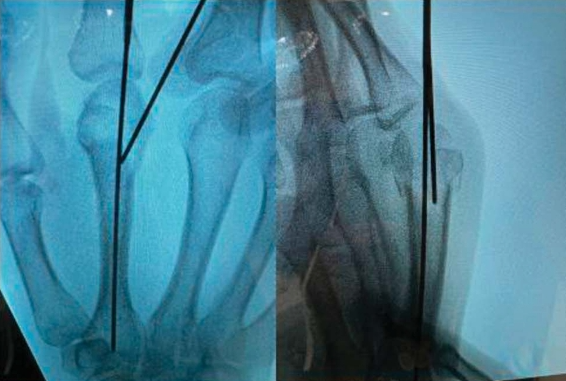

3. Percutaneous K-Wire Fixation for Metacarpal Neck Fractures

Percutaneous K-Wire Fixation (1).webp

Percutaneous K-Wire Fixation2 (1).webp

4. Percutaneous K-Wire Fixation for Adjacent Metacarpal Neck and Base Fractures